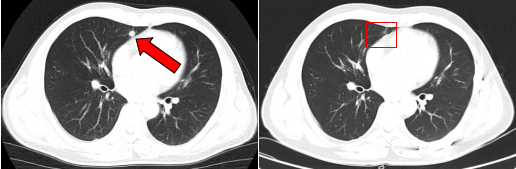

治疗前后的肺部转移病灶图像对比( 左:治疗前,右:治疗后)

2018年2月,复查MRI提示颈部淋巴结复发,患者在我院接受了淋巴结清扫术;2020年1月,胸部CT提示肿瘤转移至双肺,病情出现进展。医疗团队启用“晚期肿瘤布拉格治疗”方案,这一创新疗法融合了精准的局部放射治疗、GM-CSF刺激骨髓抗原释放技术,并联合免疫治疗,三管齐下。在完成14个周期治疗后,肺转移灶的代谢活性显著降低。

2024年,肺部转移灶出现进展,纵隔淋巴结转移和颈部淋巴结复发。邱素芳主任医师再次组织多学科会诊,为患者制定全新的治疗方案,将免疫治疗与精准的局部放疗相结合,并辅以口服化疗药物维持治疗。这种疗法副作用较小、疗效较持久。目前,其病情稳定,生活质量得到较大提高。